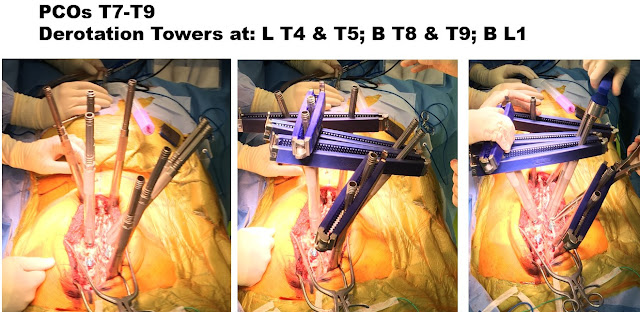

In order to maximize 3-dimensional correction and long-term outcome, while minimizing need for any additional surgeries the plan was to do a T3 to L1 posterior spinal fusion. T7-T8 and T8-T9 PCOs, or posterior column osteotomies were also performed. These osteotomies (PCOs) are done at the time of surgery to increase spine flexibility in all 3 planes, to maximize spinal deformity correction to as close to “normal” as we can safely achieve.

The silver towers or rods are attached to the screws (picture on left), and then these towers are connected together to improve strength of the spine fixation (middle picture). This connection process, for this patient, make 3 groups, one for each curve. These 3 groups of towers/screws are then rotated back toward normal (picture on right). You can see the different position of the middle group, relative to the other two groups, between the middle and right-sided pictures. Once rotated to the improved position (right picture) the screws are then tightened down, and much more work is done in surgery to 3-dimensionally improve and balance the spine.